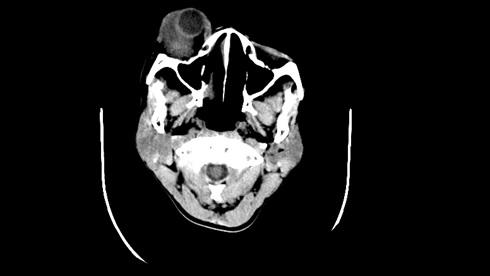

*Case 5 : Dr Garba Dahiru Waziri

email: wazirdg@gmail.com

Clinical detail: A 45-year-old female patient who presented to our hospital with history of progressive proptosis of the right eye of 8 years duration and progressive loss of vision of 3 years duration. There was associated history of periorbital pain and discomfort as the proptosis progressed. She gave no medical history of trauma, instrumentation or blunt injury to the face. There were no other contributory complaints.

Please, consult the images and virtual slides of Case 5 below.